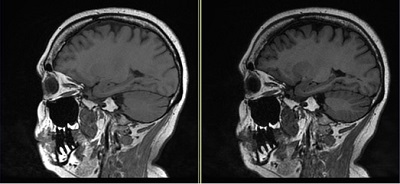

- T1FLAIR: use to provide better T1 contrast with suppressed CSF.

Figure 4. Cube comparison with and without T1 FLAIR Imaging Option

Table 4. Image legend Image Description Left Cube image with no T1 FLAIR Imaging Option. Right Cube with T1 FLAIR Imaging Option demonstrates better gray matter/white matter contrast in comparison to Cube T1 image.